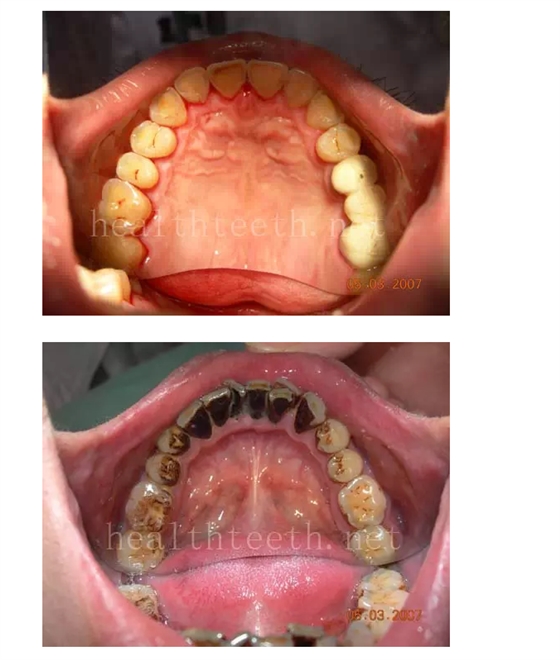

一、齲齒

18歲全口牙牙根部的早期齲

18歲孩子的口腔狀況

30歲人的口腔狀況

40歲人的口腔狀況